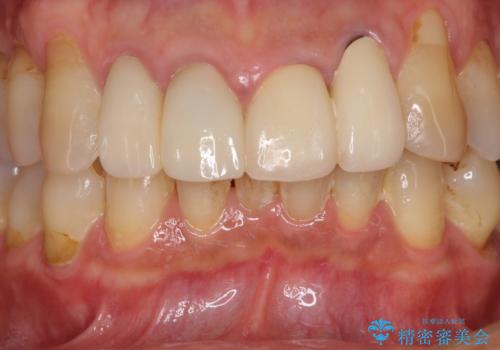

- 昨年治療した前歯の根尖部に痛みを感じ、ラバーダムや顕微鏡を用いた根管治療を希望されて、転院された患者様です。

前医にて神経を取り除いた処置を行った際、ラバーダムが使用されなかったとのことで転院されてきました。

根管治療を実施した後、オールセラミッククラウンに補綴することとしました。

前歯のセラミッククラウンを装着したばかりであったので、根管治療のためにクラウンを壊さなければならないことを残念に思っていらっしゃいました。

しかし、根管治療後はすぐに痛みがひき、治療を受けられて良かったとのことでした。